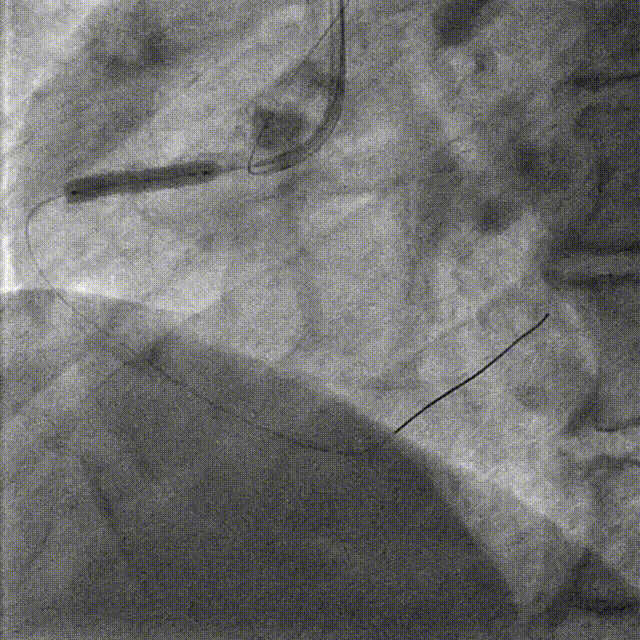

PCI-RCA TR, 7F JR4.0 ROTA with 2.0mm burr

Angiography post-ROTA

Lesion preparation NC 2.5*12mm → Cutting balloon 4.0*10mm @ 12atm

Angiography & DCB Angioplasty DCB 4.0*20mm @ 8atm, 60s

DES Deployment & Optimization DES 4.0*20mm → NC 4.0*12mm @ 20atm

Final Results